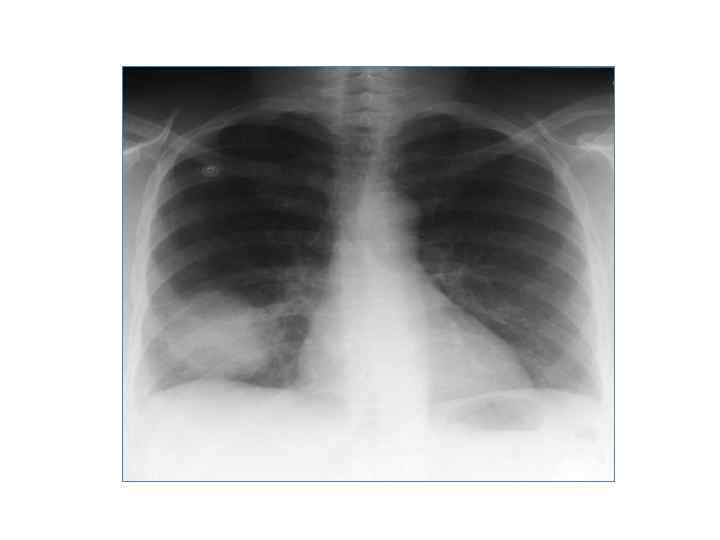

Выделяют три формы рака легкого: • Центральный (эндобронхиальный, перибронхиальный, смешанный) • Периферический (шаровидная, пневмониеподобная, полостная формы) • атипические формы (медиастинальный, верхушки, первичный канцероматоз)

Периферический рак

Шаровидная форма